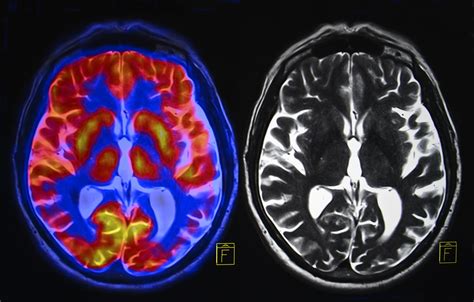

An Amyloid PET scan is a specialized type of medical imaging that uses positron emission tomography (PET) to visualize the density and distribution of beta-amyloid plaques in the brain. Beta-amyloid is a protein fragment that naturally occurs in the body, but in people with Alzheimer’s disease, these fragments clump together to form "plaques." These plaques accumulate between neurons and are believed to disrupt cell-to-cell communication, eventually leading to the cognitive decline associated with dementia.

During the procedure, a radiotracer is injected into the patient's bloodstream. This tracer is designed to bind specifically to amyloid plaques. Once the tracer circulates through the brain, the PET scanner detects the radioactive signal, creating detailed images that allow neurologists to see where these plaques have aggregated.

The results of an Amyloid PET scan are generally reported as "positive" or "negative." A positive result indicates that a significant amount of amyloid plaque is present, which is consistent with Alzheimer’s pathology. A negative result means that amyloid levels are within the normal range for the patient’s age, which strongly suggests that the cognitive decline is likely caused by something other than Alzheimer’s disease.

It is vital to recognize that a positive scan is not a "guarantee" of future dementia. Some older adults have amyloid plaques in their brains but do not exhibit significant cognitive impairment. Therefore, the scan must always be interpreted within the context of the patient's daily functioning and physical neurological exam.